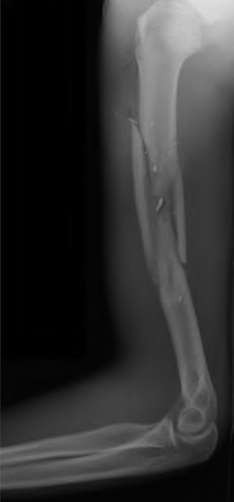

A 20-year-old park ranger trips and falls onto his right wrist with the wrist in extension and pronation. The local urgent care orders both radiographs and a CT, which you review and determine to be normal. The patient complains of ulnar-sided wrist pain. On exam, his tenderness is localized to the fovea. Ulnar deviation also causes him pain. There is no snapping sensation with wrist supination, flexion, and ulnar deviation. He otherwise has 5/5 strength to his first dorsal interosseous muscle with 4mm static two-point discrimination on the ulnar side of the 4th digit. Which of the following injuries is most likely responsible for his symptoms and exam?